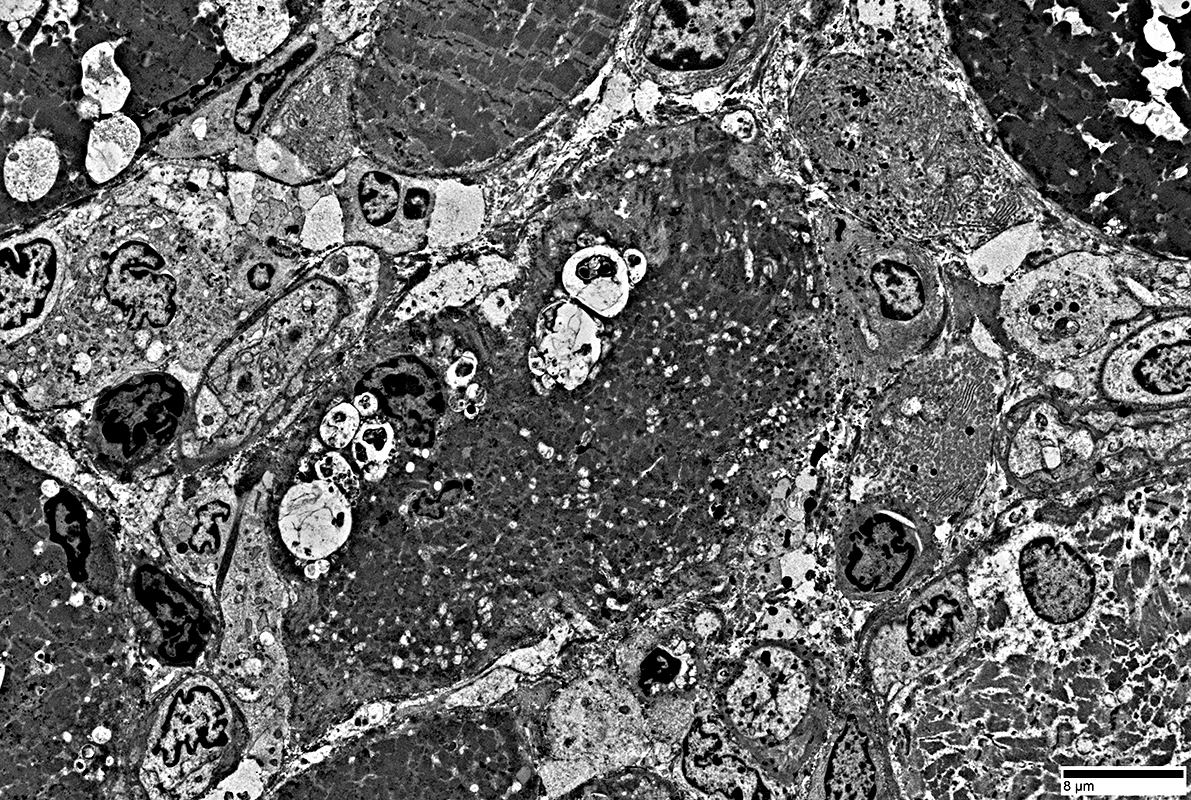

IM-VAMP: Muscle fiber pathology + Focal invasion of Muscle fiber by cells

Cytoplasmic inclusions: Several types

Myeloid

Membrane-like

Tubulo-Vesicular

Filamentous

Autophagic debris

Lipid-like bodies

Mitochondria

Endomysial capillaries

Normal size & walls

Inclusions & Vacuoles: Different Types in muscle fibers in IM-VAMP

- Filamentous (Black arrow; Above)

- Osmophilic (Red arrow; Above): Possible remanants of nuclear membranes

- Autophagic

- Membrane-like (White arrow; Above): Multilayered; Irregular shapes; May be within larger, "vacuolar", structures

- Tubulovesicular material (Below)

From: R Schmidt